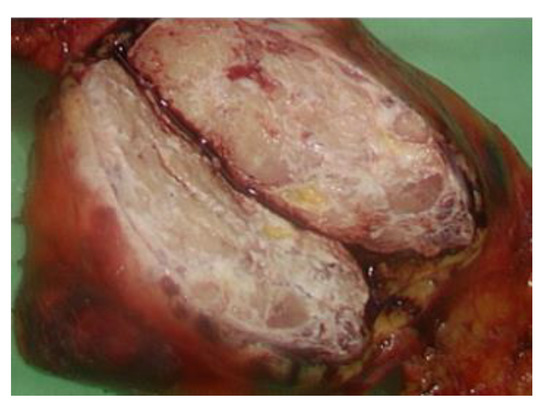

Background and Objectives: Thymomas are associated with a high frequency of paraneoplastic manifestations. Paraneoplastic syndrome (PNS) with thymoma presents a challenge to clinicians because of the need to decipher the association between the presenting symptoms and the underlying tumor. The condition most [...] Read more.

Background and Objectives: Thymomas are associated with a high frequency of paraneoplastic manifestations. Paraneoplastic syndrome (PNS) with thymoma presents a challenge to clinicians because of the need to decipher the association between the presenting symptoms and the underlying tumor. The condition most commonly noted in patients with PNS with thymoma is myasthenia gravis. Other common autoimmune diseases that may present as PNS include systemic lupus erythematosus, pure red cell aplasia, and Good syndrome. Seventy-six percent of patients with PNS-associated thymoma experience resolution of PNS after curing thymoma. Materials and Methods: A 37-year-old man with a two-month fever accompanied by polyarthritis accidently found thymoma after contrast computed tomography scans of his chest. He accepted Video assisted thoracoscopic surgery with resection of thymoma. Results: Fever and polyarthritis resolved after operation but recurred in five days due to cytomegalovirus viremia, which might be predisposed by previous antibiotics treatment before the diagnosis of thymoma. Conclusion: Patients with a thymoma also have a high frequency of PNS, and the most frequent condition found in patients with PNS-associated thymoma is myasthenia gravis. Fever with polyarthritis has been rarely reported as a symptom of PNS-associated thymoma. Here we reported an unusual case of PNS mimicking reactive arthritis with thymoma, as diagnosed based on the patient’s clinical progression, imaging examination, and laboratory tests. The patient died of his comorbidities, and his death may have been related to long-term antibiotic use and consequent intestinal dysbiosis. This challenging case may help to inform clinicians of the need for detailed work-up of fever with unknown origin in the presence of chronic polyarthritis to prevent the overdiagnosis of inflammatory arthritis or rheumatic disease and avoid further comorbidities. Detailed work-up should include the patient’s history of infections, inflammation, and malignant or nonmalignant tumors. Full article

Show Figures

Figure 1